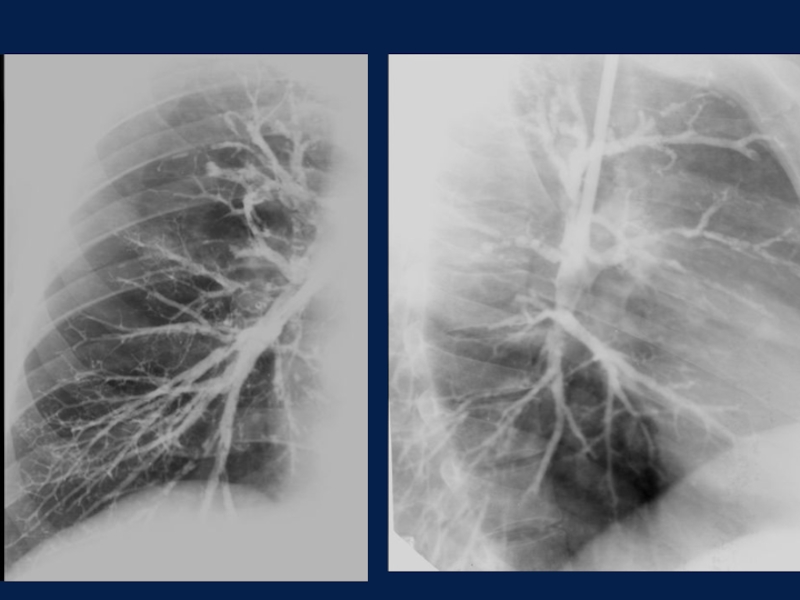

Слайд 14Методика рентгенологического исследования с контрастированием крупных и средних бронхов на

всем их протяжении после предварительной анестезии

Бронхография

Методика рентгенологического исследования с контрастированием крупных и средних бронхов на всем их протяжении после предварительной анестезииБронхография

Слайд 15 В отношении каждого бронха учитывают:

а) положение, б) форму, в)

ширину просвета, г) характер заполнения, д) угол отхождения и характер

ветвления, е) контуры, ж) локализацию и характер отклонений от нормальной картины.

В отношении бронхов, не заполнившихся контрастным веществом, учитывают положение, форму и очертания их культи, состояние окружающей бронх легочной ткани.

План изучения бронхограммы:

В отношении каждого бронха учитывают: а) положение, б) форму, в) ширину просвета,  г) характер заполнения, д)